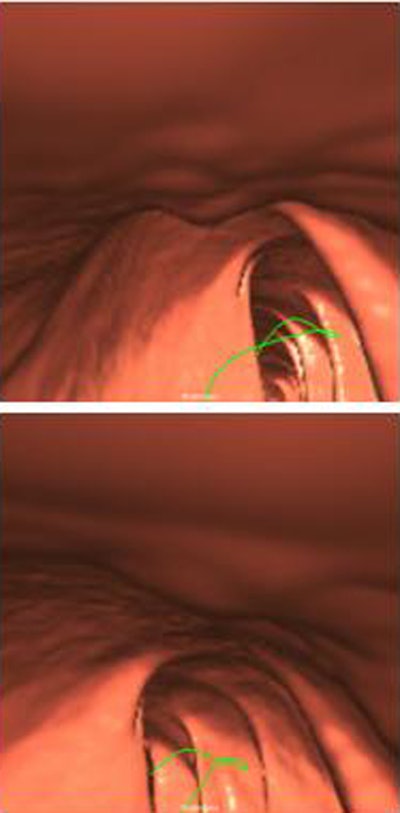

The automated polyp measurement scheme (Yao J et al, in press) utilizes a "pattern-recognition topographic height method similar to what you might see in a geographic terrain map where you have different curves showing different lengths of structures on the terrain," Summers said. When the technique is applied to colonic mucosa, curves depict the polyp contours as curves and the area around the base as dots, he noted.

Polyp height was measured as the distance between the peak and the base of the polyp. Width was calculated as the maximum difference of points on the base. Measurements on the investigational software application (Viatronix, Stony Brook, NY) were compared with calibrated guidewire measurements at optical colonoscopy.

| Above, an adenoma measuring 8 mm at optical colonoscopy (per calibrated guidewire) measured 1.9 mm and 1.8 mm high and 7.7 mm and 7.0 mm wide in supine (top) and prone (bottom) CTC (per automated measurement algorithm), respectively. Below, a hyperplastic polyp measuring 8 mm at optical colonoscopy measured 2.46 mm and 1.65 mm high and 9.89 mm and 10.32 mm wide in supine (top) and prone (bottom) CTC images, respectively. The automated polyp measurement scheme utilizes a pattern-recognition topographic height method similar to that of a terrain map. Polyp contours are depicted as curves. All images courtesy of Dr. Ronald Summers, Ph.D. |